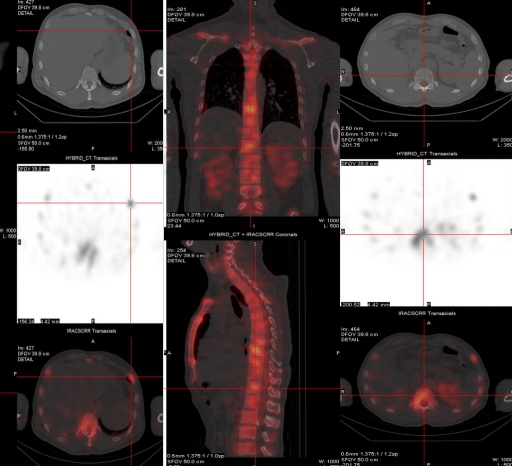

(病例一)患者,男,39岁,右肺门中央型肺癌T3N2MX(IIIB期),为明确是否有骨转移来我科就诊。MIP图示:额骨右侧、C6、T12、左侧第6肋,右侧第7、8肋多发小片状放射性摄取增高灶,SPECT/CT融合图示:额骨右侧、C6、T12、左侧第6肋,右侧第7、8肋未见明显骨质破坏。结合肺癌病史,考虑额骨右侧、C6、T12、左侧第6肋,右侧第7、8肋多发骨转移。如下图: